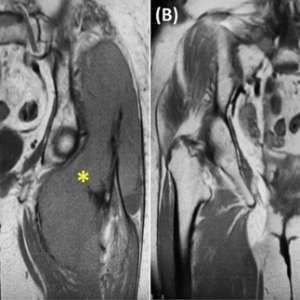

Образование в ягодичной области у пациента с множественной миеломой

Женщина, 78 лет

В анамнезе множественная миелома и AL-амилоидоз. В 2022 году проведен курс лечения бортезомибом, леналидомидом и дексаметазоном (VRD), отмечен полный ответа на лечение.

Жалобы на появление образования в ягодичной области, пациентка отмечает быстрый рост образования за 2 месяца. Она регулярно наблюдается в гематологическом отделении и амбулаторной клинике и в настоящий момент не получает поддерживающую терапию.